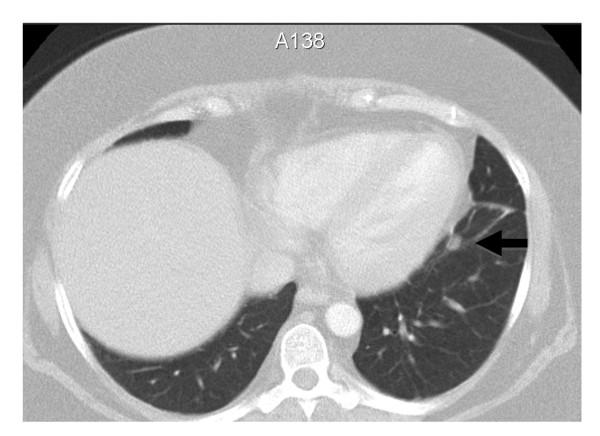

A 37-year-old Arabian woman presented with 12 months of progressive Cushing's syndrome-like symptoms. Biochemical evaluation confirmed adrenocorticotropic hormone -dependent Cushing's syndrome. However, the anatomical site of her excess adrenocorticotropic hormone secretion was not clearly delineated by further investigations. Magnetic resonance imaging of our patient's pituitary gland failed to demonstrate the presence of an adenoma. Spiral computed tomography of her chest only revealed the presence of a non-specific 7 mm lesion in her left inferobasal lung segment. Functional imaging, including a positron emission tomography scan using 18-fluorodeoxyglucose and gallium-68-DOTA-D-Phe1-Tyr3-octreotide, also failed to show increased metabolic activity in the lung lesion or in her pituitary gland. Our patient was commenced on medical treatment with ketoconazole and metyrapone to control the clinical features associated with her excess cortisol secretion. Despite initial normalization of her urinary free cortisol excretion rate, levels began to rise eight months after commencement of medical treatment. Repeated imaging of her pituitary gland, chest and pelvis again failed to clearly localize a source of her excess adrenocorticotropic hormone secretion. The bronchial nodule was stable in size on serial imaging and repeatedly reported as having a nonspecific appearance of a small granuloma or lymph node. We re-explored the treatment options and endorsed our patient's favored choice of resection of the bronchial nodule, especially given that her symptoms of cortisol excess were difficult to control and refractory. Subsequently, our patient had the bronchial nodule resected. The histological appearance of the lesion was consistent with that of a carcinoid tumor and immunohistochemical analysis revealed that the tumor stained strongly positive for adrenocorticotropic hormone. Furthermore, removal of the lung lesion resulted in a normalization of our patient's 24-hour urinary free cortisol excretion rate and resolution of her symptoms and signs of hypercortisolemia.